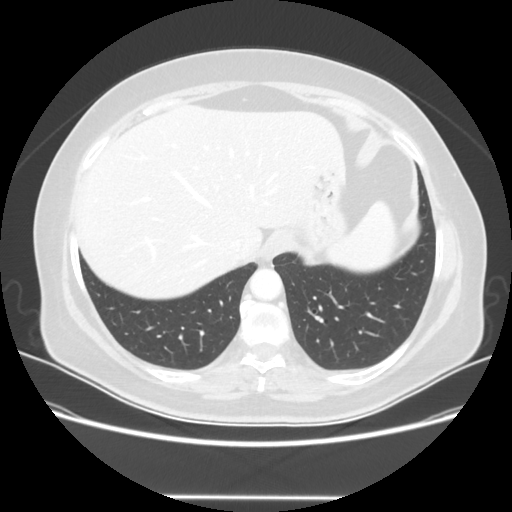

Original NATIVE CT scan (input)

Full window (WL 1023.5, WW 4095 β†’ Low βˆ’1024, High +3071)

Lung window (WL -600, WW 1500 β†’ Low βˆ’1350, High +150)

Mediastinum window (WL 40, WW 400 β†’ Low βˆ’160, High +240)